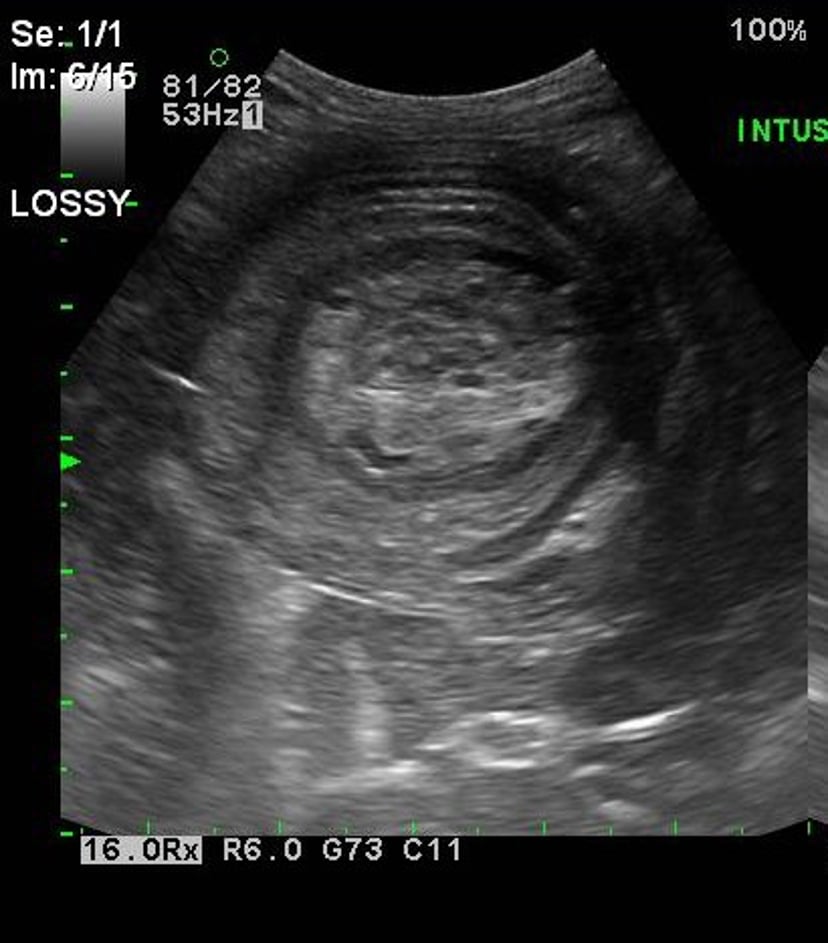

Intestinal intussusception, ultrasonogram, dog

Ultrasonographic image of a 10-month-old mixed-breed dog with an ileocecocolic intussusception. Note the targetlike concentric rings representing the invaginated tissue.

Courtesy of Dr. Kevin Winkler.